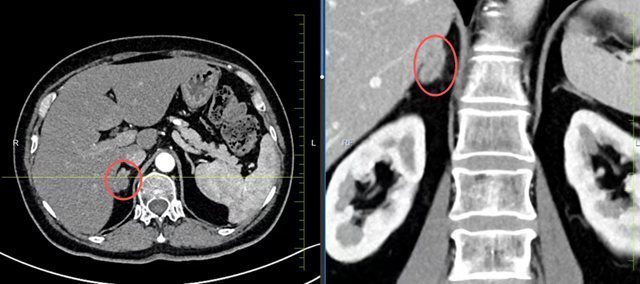

患者因右侧肾上腺肿瘤伴血肿入院,合并2型糖尿病且血糖控制不佳。